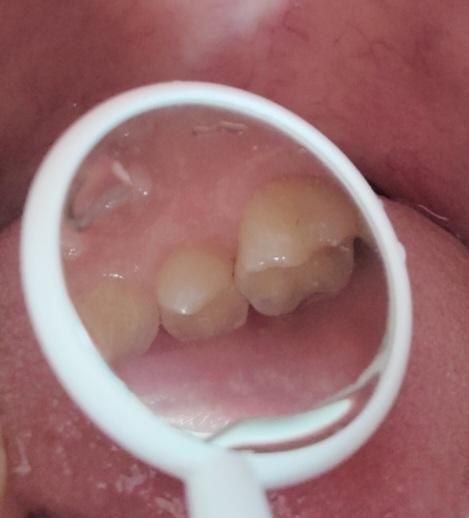

소구치와 대구치 사이가 까맣게 보여요.충치일까요?

제가 양치하고 치아를 살펴보니 소구치와 대구치 사이가 까맣게 보였습니다.

• 3번 째 사진